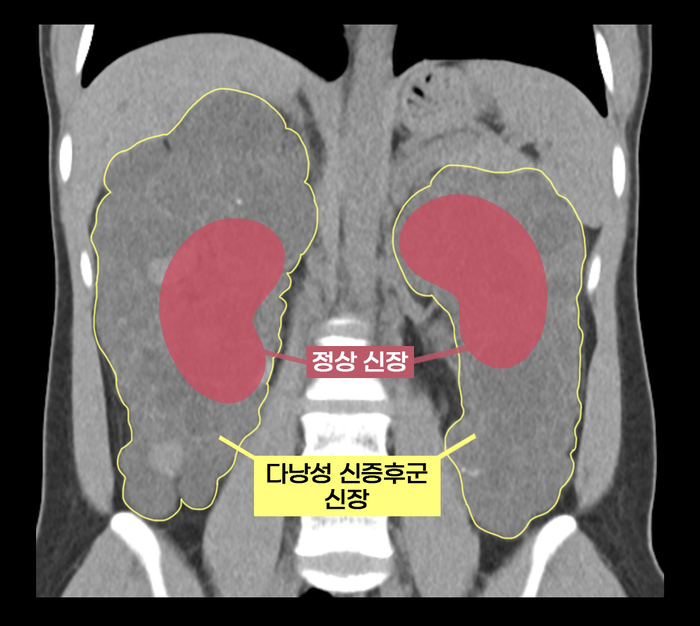

실제 다낭성 신증후군 환자의 신장과 정상 신장 비교(수많은 낭종으로 울퉁불퉁하고 크기도 비대해진 상태) 보통의 만성 신부전 환자는 신장이식을 할 때 기존 신장을 그대로 두지만,다낭성 신증후군 환자는 들어내야 한다. 이미 7배나 커진 상태여서 건강한 신장이 들어갈 자리가 없기 때문이다. 기존 신장을 제거하면 낭종 감염과 낭종 파열로 인한 출혈,신장암 발병 등의 합병증 위험도 줄일 수 있다.